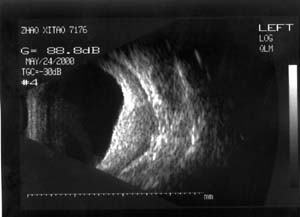

1 患者男性,32岁。998月发现左眼球突出,当时按眶内炎症治疗无效9912月左眼开始充血,反复发作(后来仅间隔1-2天),头痛。曾按“结膜炎、眼眶炎症”等治疗无效。20004月经CT检查发现左眼球外侧肿物,诊断:眼内肿物、眶内炎性假瘤?随来我院。入院检查:视力(戴镜)右眼1.0,左眼0.3,不能矫正。左眼睑肿胀,结膜混合充血,结膜下血管怒张(图1)。角膜正常,屈光间质清楚。眼底为高度近视眼底表现(-10D),眼球壁内下方600-900自视盘下方开始隆起(约+6D)。眼球突出4mmB超及标准化A超显示左眼球内下方及下方巩膜肥厚,最厚处达7mm,可见明显筋膜囊水肿(图2)。CT显示左眼球内下方巩膜增厚,并向眼内隆起,筋膜囊水肿(图3)。

2 B

超显示眼球壁明显增厚